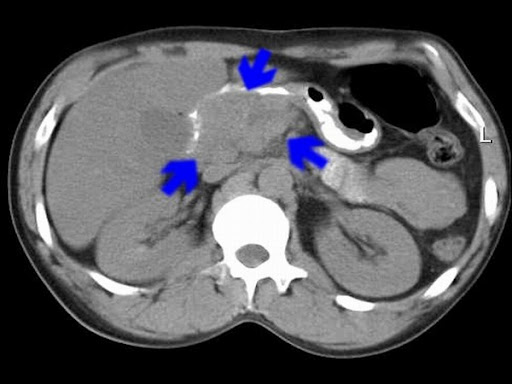

Компьютерная томография при псевдотуморозном панкреатите хорошо выявляет следующие анатомические признаки:

В нативном режиме определяется увеличение головки поджелудочной железы с пониженной плотностью и неровными, но не инфильтративными краями.

В режиме сканирования мягких тканей визуализируется диффузная инфильтрация парапанкреатической клетчатки без чётких границ и с вовлечением дуоденальной стенки.

В режиме с контрастированием фиксируется слабое, равномерное или слегка гетерогенное накопление контрастного вещества в зоне воспалительного узла.

Фиксируется деформация или сужение общего желчного протока на уровне головки железы без признаков его инвазии или обструкции твёрдой опухолью.